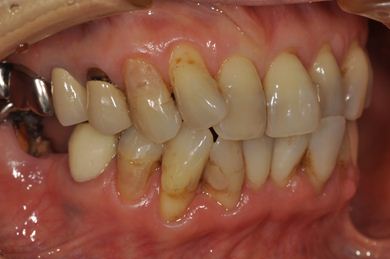

抜歯即日スピードインプラント+セラミック治療

| 性別/年齢 | 女性 / 52歳 | ||||||||||||||||||||||||||||||||

| 主訴 | 引っ越しで治療が途中になっている歯の治療と、他の歯にもトラブルが起こったため相談したい。 | ||||||||||||||||||||||||||||||||

| 治療内容 | インプラント2本(抜歯即日スピードインプラント)、ハイブリッドセラミッククラウン5本(セラミック用土台2本)、ハイブリッドセラミックインレー1本 | ||||||||||||||||||||||||||||||||